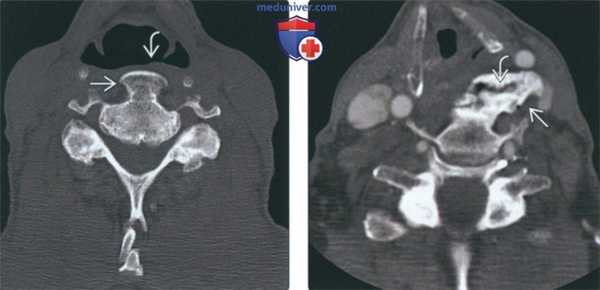

(Слева) На аксиальной КТ в костном окне определяется ОЗПС в сочетании с ДИСГ. В самых верхних отделах ОЗПС выглядит как пальцевидное выбухание, обычно не контактирующее с позвонком.

(Справа) На аксиальной КТ в костном окне определяется выраженная оссификация ЗПС в основании С2, сливающейся с задней кортикальной плааинкой позвонка. Результирующее сужение позвоночного канала приводит к тяжелому сдавлению спинного мозга и симптомам миелопатии, наличие которых является одним из немногих показаний к хирургическому вмешательству.